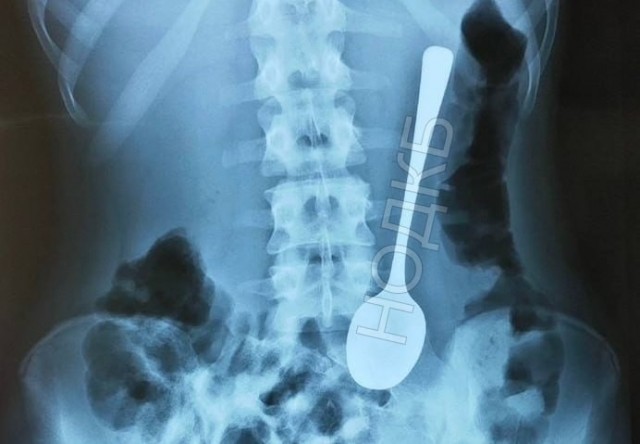

«Позвонили хирурги, рассказали про ребёнка в приёмном покое с десертной ложкой в желудке. Я подумал, что это шутка и меня хотят поздравить с праздником, но нет!» — рассказал завотделением НОДКБ Александр Дворянинов.

Как пишет главред «Стационар пресс» Алексей Никонов, ложку быстро достали с помощью гастроскопа. И даже не понадобился наркоз!

Игрушки были, монеты были, но ложка... Именно ее проглотил юный нижегородец.